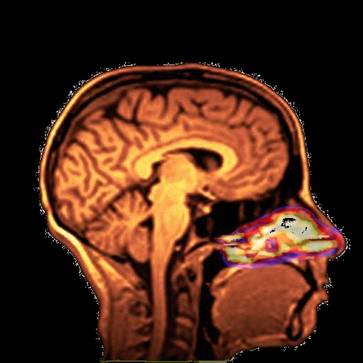

Several inhaled drug formulations were studied by radiolabeling the active ingredient (several different steriods) with C-11 or F-18, formulating that ingredient as the dosage form (different MDI, DPI, and nebulizer formulations), and performing quantitative PET studies of the regional biodistribution and kinetics.

Click on images to see additional examples, larger versions, and videos.